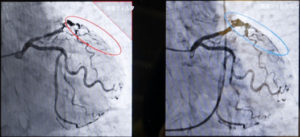

同一患者データ 画像左:従来システム 画像右:Alphenix